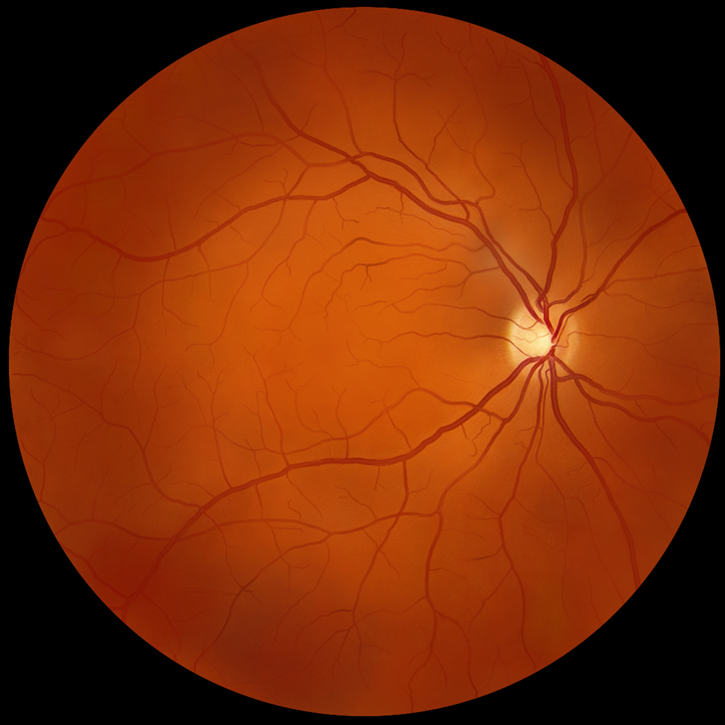

眼睛是人类最为精细复杂的器官

眼科手术机器人的研发对于解决眼底和显微手术中的痛点至关重要。迪视医疗凭借其个性化的医工结合、基于主从控制的多自由度和独创的柔性结构技术,成功实现高达3微米的运动精度。公司在产品技术和研发进度方面保持全球领先地位。自2023年7月“迪视微锋”眼科手术机器人在浙江省人民医院完成亚洲首例人体临床应用病例后,已成功完成多例科研临床病例,术后效果良好。目前,公司正式启动NMPA注册的临床试验工作,以进一步验证其产品的安全性和有效性。此外,公司的显微外科手术机器人也已进入样机开发阶段,标志着迪视医疗在医疗机器人领域不断推进创新,为未来的医疗技术发展做出贡献。